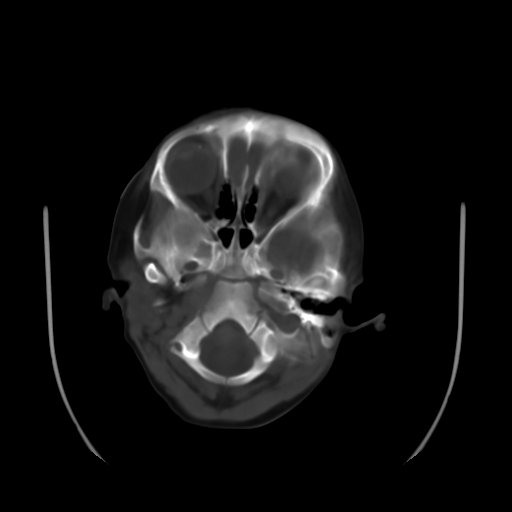

以下是引用深泽交通医院在2009-10-16 8:25:00的发言:[br]右眼环出血伴异物

以下是引用卜一在2009-10-16 15:01:00的发言:[br]右眼球挫裂伤伴异物!

以下是引用拾荒者在2009-10-17 18:38:00的发言:[br]鼻面部皮下积气,右侧睑缘及眼球壁高密度异物影,左侧眼球壁晶状体内侧缘处是圆形低密度影。低密度异物?应提请眼科医生注意。